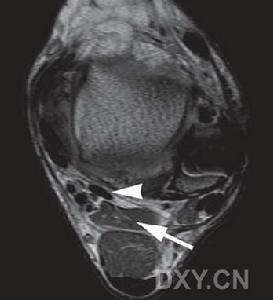

拇長屈肌拇長屈肌是屈拇指末節的唯一骨骼肌。據傳統描述,它位居前臂屈側深層的橈側份,近側附著於橈骨前面和鄰近的前臂骨間膜,其長腱經腕管,拇指腕掌關節,向遠側附著於拇指末節指骨底。然而,將近一個世紀以來,不斷有報導此肌在前臂部具有附著於尺側方的。